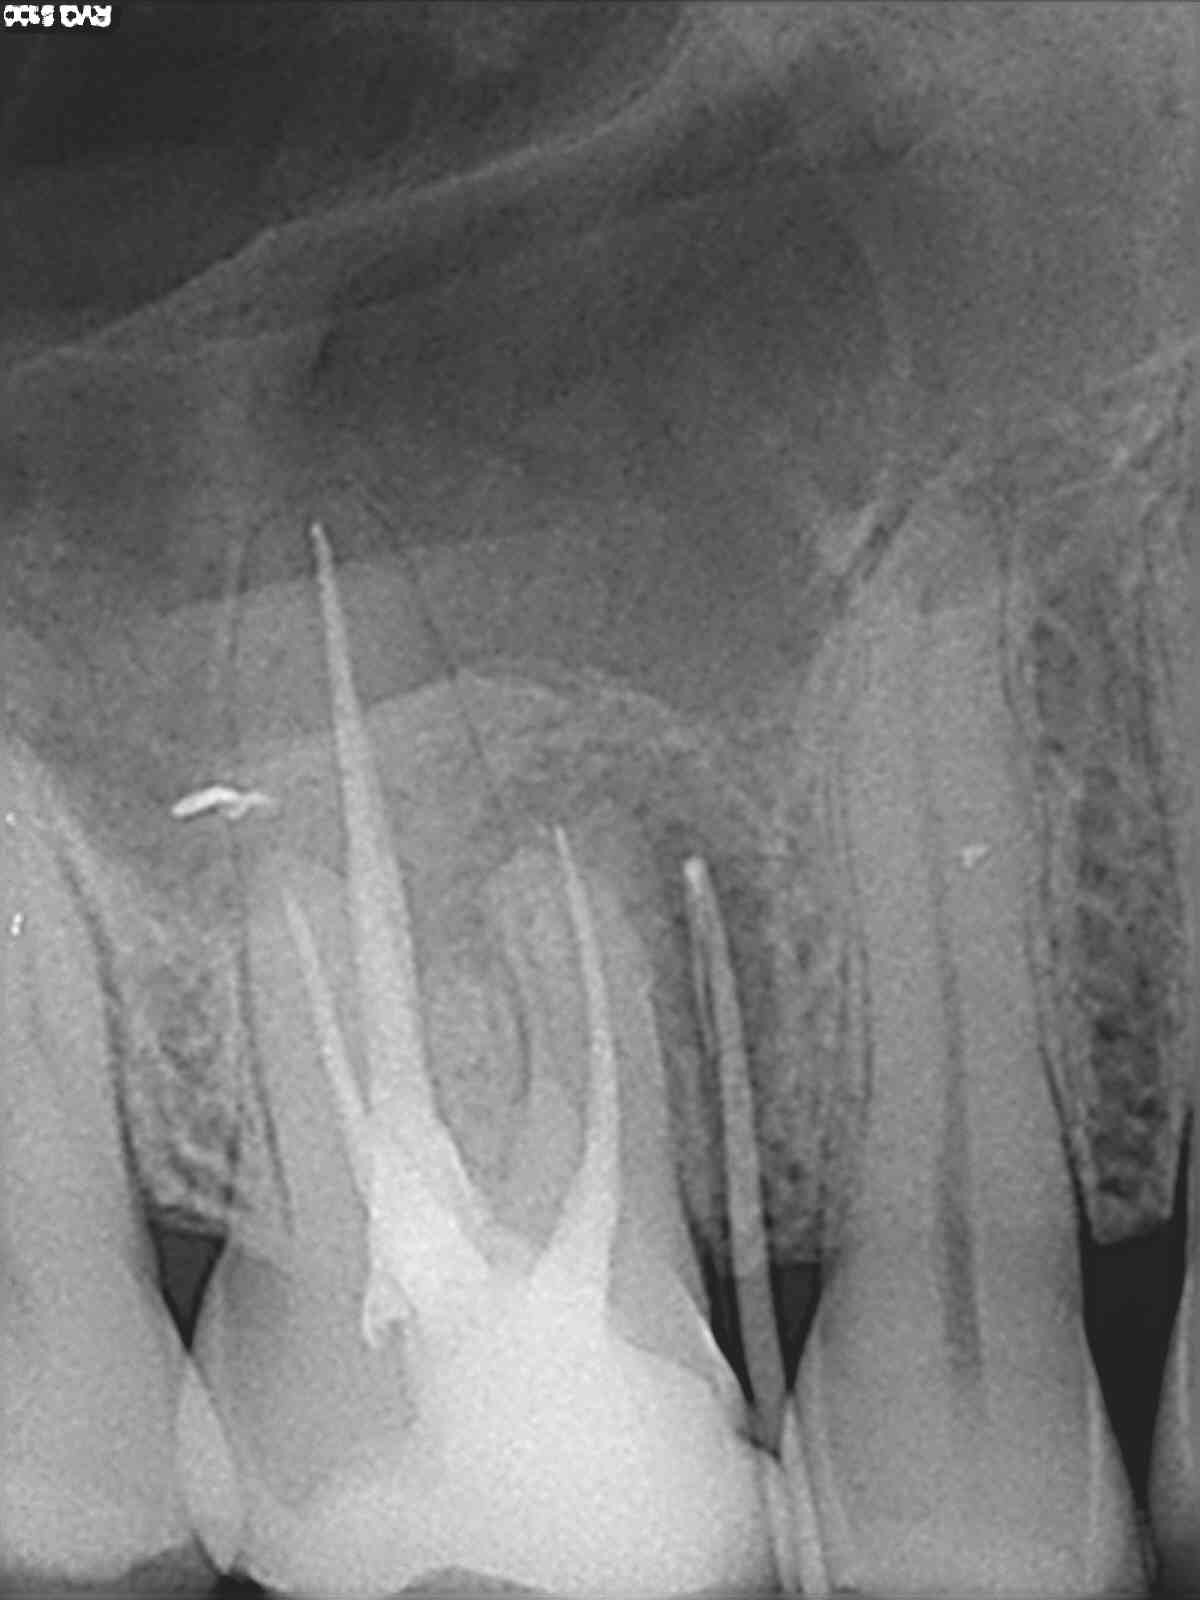

Все началось с того, что мне 13 июля небрежно за 5 минут запломбировали каналы в 1 посещение и вывели за верхушку корня силлар Н+ и гуттаперчевые штифты. Рентген в день пломбировки.